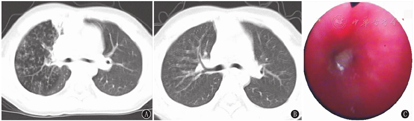

67例患儿胸部高分辨CT均表现为树芽征、小叶中心结节。19例(28.4%)并少量胸腔积液;22例(32.8%)并少量肺实变或不张;单侧病变22例(32.8%),双侧45例(67.2%);累及单个肺叶6例(9.0%),累及2个肺叶23例(34.3%),累及≥3个肺叶38例(56.7%),其中累及3个肺叶20例(29.9%)、4个肺叶12例(17.9%)、5个肺叶6例(9.0%)(图1A和图2A)。

35例(52.2%)患儿支气管镜下特点:71.4%(25/35例)表现为白色絮状、条索状分泌物(图1C);17.1%(6/35例)表现为黏液栓堵塞管腔(图2C),其中33.3%(2/6例)为塑型性分泌物,33.3%(2/6例)为塑型性分泌物合并远端通气不良,33.3%(2/6例)合并肉芽组织增生(图2C);10.9%(4/35例)表现为结节样凸起合并肉芽组织增生。

胸部高分辨CT是诊断细支气管炎的主要依据,包括直接征象和间接征象两大类特征性影像。细支气管扩张征(细支气管壁增厚和管腔扩张所致)、树芽征和小叶中心结节为直接征象,马赛克征及气体滞留征为间接征象[16]。本研究67例患儿胸部高分辨CT均表现为树芽征、小叶中心结节,部分合并少量胸腔积液(28.4%),当病变累及肺泡及其周围组织时,可出现肺实变或不张(32.8%)。肺部以双侧弥漫性病变为主(双侧病变45例,≥3个肺叶者38例),也可呈单侧局灶病变或弥漫性病变(单侧病变22例,单个肺叶者6例)。